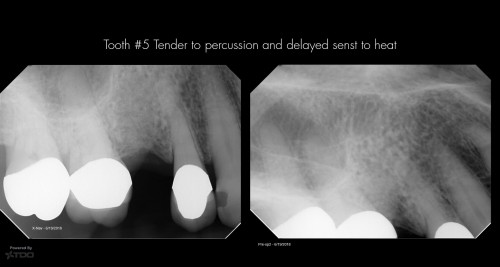

Dual Entry Access

66 yof. SIP following crown preparation and removal of caries. The permanent crown is ready […]